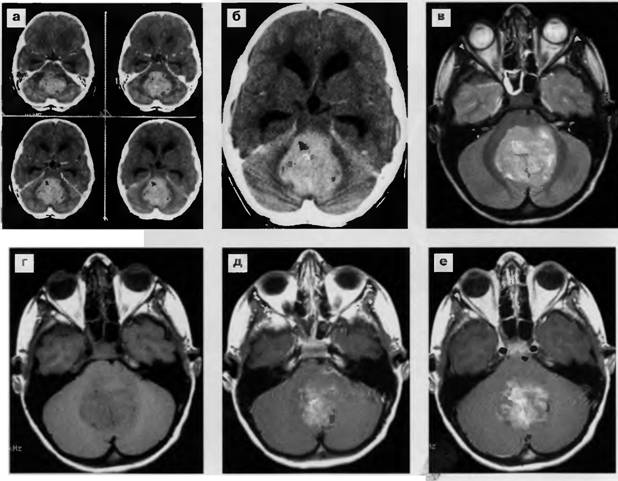

Правильна і своєчасна діагностика дозволяє провести адекватне лікування, тим самим збільшивши шанси пацієнта на одужання. Для виявлення метастазів в головному мозку використовують такі методи, як:

• Комп'ютерна томографія . Даний рентгенологічний метод дослідження дозволяє отримати пошарове картину тканин і органів. Обов'язково використовувати контрастне посилення при проведенні томографії.

• Магнітно-резонансна томографія . Даний метод застосовується найчастіше, так як має високу точність і чіткість одержуваного зображення. І, крім того, пацієнт не піддається дії випромінювання.